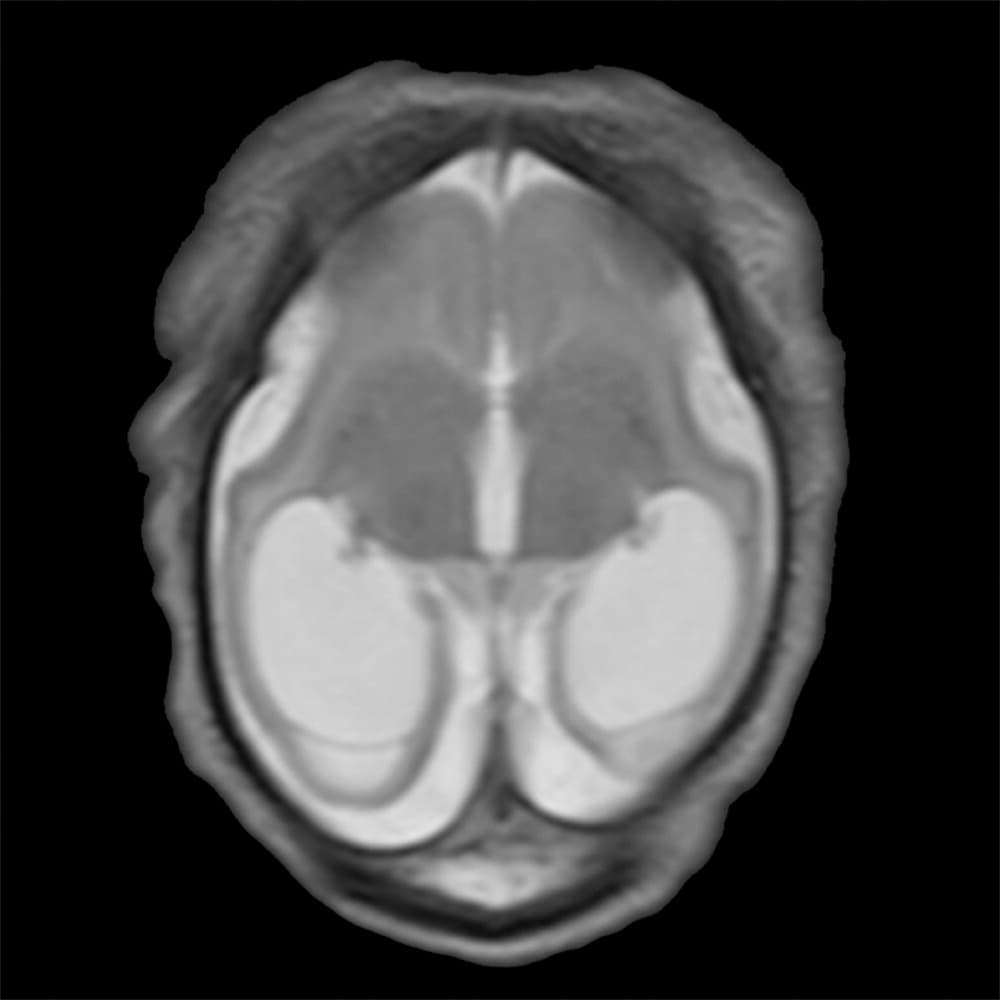

Investigadores brasileños difundieron este martes el mayor número hasta ahora disponible de imágenes computarizadas, resonancias magnéticas y ultrasonidos, de bebés y fetos infectados con el virus del Zika. El daño es mucho mayor del que anticipaban.

Así describe la radióloga brasileña Fernanda Tovar-Moll lo que vio al analizar centenares de imágenes computarizadas, resonancias magnéticas y ultrasonidos de 45 bebés que se contagiaron de zika en el vientre materno en el estado de Paraíba, en el noreste del país, donde el brote ha sido severo.

La mayoría nació con microcefalia, cuya característica más llamativa es que tienen el cerebro y la cabeza más pequeña. Pero muchos sufren una escala y severidad de daño mucho peor en partes importantes del cerebro como el cuerpo calloso, que conecta los dos hemisferios; el cerebelo, que juega un papel significativo en el movimiento, equilibrio y habla; y los ganglios basales, que controlan el pensamiento y la emoción.

Tovar-Moll es coautora de un estudio publicado el martes en la revista Radiology y fue liderado por la doctora Patricia Soares de Oliveira-Szejnfeld, a quien se le da crédito por establecer el vínculo entre el zika y la microcefalia en Brasil.